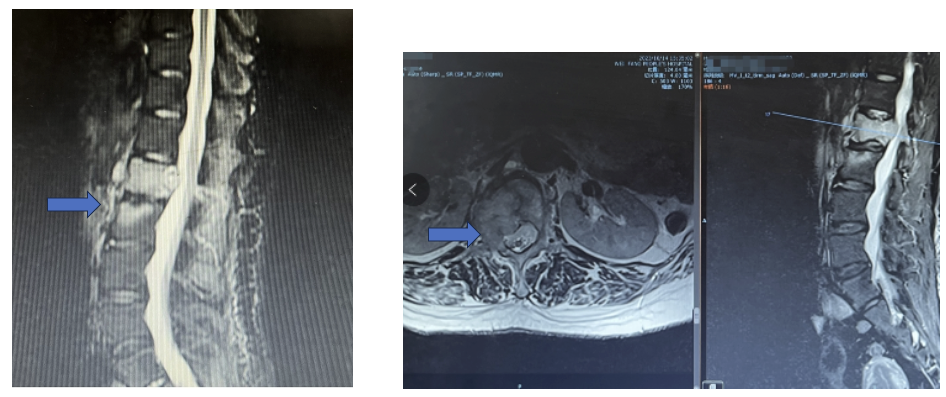

胸腰椎MR示: L1椎体及附件、L2椎体、L3棘突信号异常,考虑转移瘤可能性大。

PET-CT示:L1骨质破坏伴代谢增高,考虑为转移所致可能性大。